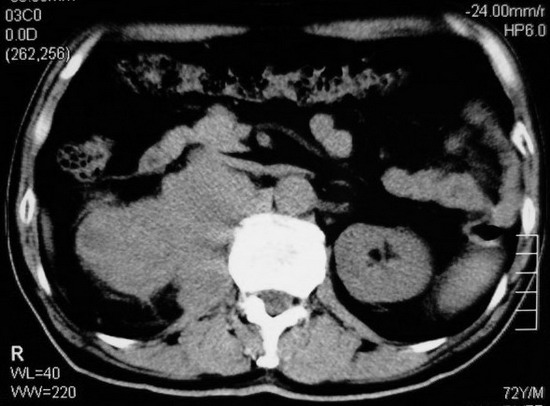

以下是引用杀毒软件在2008-11-17 19:15:00的发言:[br]考虑------右肾癌合并肾静脉---同侧肾上腺受侵可能性大

以下是引用zjzjr在2008-11-17 20:45:00的发言:[br]考虑------右肾癌合并肾静脉---同侧肾上腺受侵可能性大及腹膜后淋巴结转移.